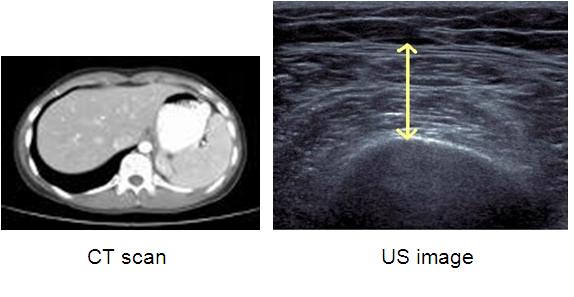

Validation of Bedside Ultrasound of Muscle Layer Thickness of the Quadriceps in the Critically Ill Patient: The VALIDUM Study

Objective : To evaluate the validity of bedside ultrasounds (US) of quadriceps muscle layer thickness (QMLT) and Multiple Frequency Bioelectrical Impedance Analysis (MF-BIA) by comparing measurements from US and MF-BIA to those estimates of lean body mass obtained from CT scans of the abdomen when done for clinical reasons.